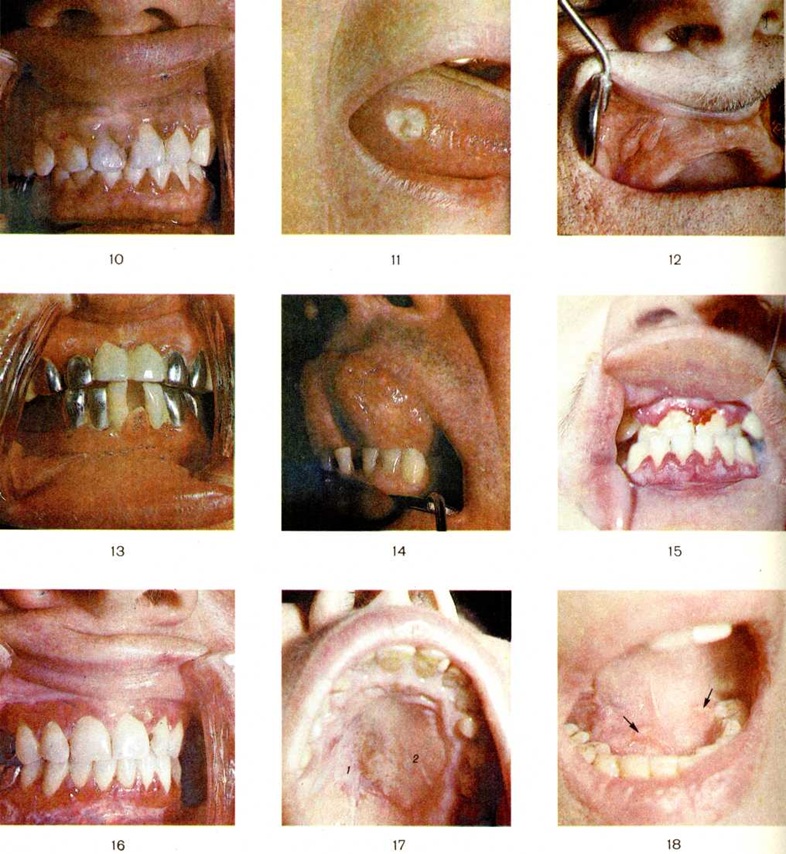

СтоматитСтоматит (греческий stoma, stomatos рот + -itis) — воспаление слизистой оболочки рта. Стоматит развивается в результате травмы слизистой оболочки рта, внедрения в неё возбудителей бактериальной или вирусной инфекции и других причин, часто является симптомом ряда общих заболеваний. В зависимости от этиологии различают следующие виды Стоматит: травматический, инфекционный (неспецифический, специфический, грибковый), аллергический, Стоматит при интоксикации солями тяжёлых металлов, Стоматит при некоторых соматических заболеваниях, дерматозах, хейлитах (смотри полный свод знаний). Кроме того, поражения слизистой оболочки рта наблюдаются при пороках развития и заболеваниях языка (смотри полный свод знаний: Язык, Глоссит), предопухолевых заболеваниях и опухолях слизистой оболочки рта (смотри полный свод знаний: Рот, ротовая полость). Травматический стоматит развивается в результате механической травмы, воздействия химических или физических повреждающих факторов. Его проявления зависят от вида раздражения, интенсивности и продолжительности действия, а также от сопротивляемости организма. Острая механическая травма довольно редка и возникает обычно случайно от прикусывания слизистой оболочки рта или ранения острыми предметами. Лечения обычно не требует. Хронический механическая травма является одной из наиболее частых причин повреждения слизистой оболочки рта. Травмирующими факторами могут быть острые края зубов и зубных протезов, зубной камень. Хронический механическая травма часто сочетается с инфицированием поражённых участков слизистой оболочки. При хронический механической травме может возникать катаральное воспаление с отёком и гиперемией слизистой оболочки рта (цветной, рисунок 10), эрозия, а затем и травматическая язва с выраженной болезненностью и воспалительной инфильтрацией (цветной рисунок 11). Травматические язвы осложняются гнойной инфекцией или кандидозом. Хронический язвы слизистой оболочки рта нередко малигнизируется. Длительное действие слабого раздражителя, например, зубного протеза, может привести к гипертрофии участков слизистой оболочки (цветной рисунок 12, 13), папилломатозным разрастаниям слизистой оболочки щёк, губ, неба. Кроме того, хронический раздражение слизистой оболочки рта может вызвать её ороговение и развитие лейкоплакии (смотри цветной рисунок 1—6 к статье Лейкоплакия). Диагноз травматического Стоматит, возникшего в результате механической травмы, ставят на основании клинические, картины. Дифференциальный диагноз травматической язвы слизистой оболочки рта проводят с трофической язвой (смотри полный свод знаний: Трофические язвы), с изъязвленной опухолью (смотри полный свод знаний: Рак), туберкулёзной и сифилитической язвами (смотри полный свод знаний: Туберкулёз внелегочный, Сифилис), хроническим язвенно-некротическим стоматитом Венсана (смотри ниже). Лечение заключается в устранении раздражителя, антисептической обработке слизистой оболочки и полоскании полости рта. При резкой болезненности показаны аппликации обезболивающими средствами. Проводят тщательную санацию полости рта (смотри полный свод знаний). Прогноз благоприятный. Химические раздражители (кислоты, щелочи и другие) при воздействии на слизистую оболочку рта вызывают поверхностный или глубокий некроз. При попадании химический вещества на слизистую оболочку необходимо быстро промыть полость рта раствором нейтрализующего вещества. Дальнейшее лечение больных с химический ожогами проводят, как при остром неспецифическом воспалительном процессе (обезболивающие, антисептические средства, средства, ускоряющие эпителизацию, высококалорийная пища). При обширных рубцах показано оперативное вмешательство. Стоматит, вызванные физическими раздражающими факторами, возникают при воздействии на слизистую оболочку рта горячей воды и других жидкостей, пара, огня, электрического тока, ионизирующего излучения в больших дозах. Лечение такое же, как при острых неспецифических воспалительных процессах. При лучевых повреждениях (смотри полный свод знаний) объем лечебный мероприятий зависит от степени и стадии лучевой болезни (смотри полный свод знаний). |

Острый герпетический стоматит встречается преимущественно у детей. Его возникновение рассматривают как проявление первичного инфицирования полости рта вирусом простого герпеса. Различают легкую, среднетяжелую и тяжёлую формы. Последние две сопровождаются выраженным нарушением состояния больного, повышением температуры тела до 38— 40°, ускорением РОЭ до 20 миллиметров/час, лейкопенией. Слизистая оболочка рта при этом отечна, гиперемирована, с большим количеством мелких везикул, быстро переходящих в эрозии, покрытые налётом (цветной рисунок 14). Локализуются эрозии преимущественно на слизистой оболочке неба, языка, щёк, губ, в переходных складках. Характерно диффузное поражение десен — острый катаральный гингивит. Могут поражаться и другие слизистые оболочки, в первую очередь желудочно-кишечные тракта.

Язвенно-некротический стоматит Венсана (язвенный стоматит, язвенно-мембранозный стоматит, фузоспирохетозный стоматит, язвенно-гангренозный стоматит, стоматит Плаута — Венсана, окопный стоматит) вызывает симбиоз веретенообразной бактерии (смотри полный свод знаний) и обычной спирохеты полости рта (фузоспирохетоз). Возникновению заболевания способствуют снижение общей сопротивляемости организма, гиповитаминоз и другие Болеют обычно лица молодого возраста. В начале заболевания повышается температура тела до 37,5—38°, отмечаются болезненность и кровоточивость десен, появляются повышенное слюноотделение, гнилостный запах изо рта. Катаральные проявления на слизистой оболочке рта переходят в язвенный процесс (гангренозный стоматит), который чаще начинается с десневого края (цветной рисунок 15) и распространяется на другие участки слизистой оболочки рта. При распространении возбудителей на небные миндалины возникает ангина Симановского — Плаута — Венсана (смотри полный свод знаний: Ангина).

Аллергический Стоматит может проявляться в виде катарального, геморрагического, пузырно-эрозивного, некротического, а также комбинированного поражения с локализацией на ограниченном участке или на всей слизистой оболочке рта. При аллергии, вызванной различными лекарственными средствами, чаще возникают катаральные и катарально-геморрагические поражения. При этом больные жалуются на чувство жжения, зуд, сухость во рту, болезненность при приёме пищи. Слизистая оболочка рта отечна, гиперемирована (цветной рисунок 16), может наступить атрофия сосочков языка (так называемый лакированный язык). При пузырно-эрозивной форме поражения слизистой оболочки на фоне выраженного отёка и гиперемии появляются пузыри, после вскрытия которых образуются эрозии, покрытые фибринозным налётом (цветной рисунок 17).

Хронический рецидивирующий афтозный стоматит — воспалительное заболевание, имеющее, как полагают, инфекционно-аллергическую природу. Оно характеризуется появлением одиночных болезненных афт (смотри полный свод знаний) на слизистой оболочке рта (цветной рисунок 18), которые через 7—10 дней заживают. Рецидивирующие афты могут быть одним из симптомов генерализованного афтоза (смотри полный свод знаний: Бехчета болезнь). Рецидивы чаще наблюдаются в весенне-осенний период. Со временем тяжесть заболевания нарастает: количество афт увеличивается, а период заживления их удлиняется до 2—4 недель, учащаются рецидивы. Иногда ремиссии вообще отсутствуют.